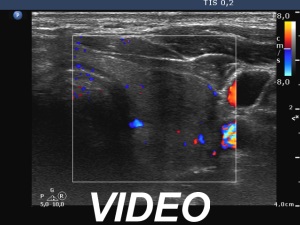

Initial examination (first row of images):

Ultrasonography: Both lobes had hypoechoic areas which showed ill-defined borders. The echogenicity index was around 50%. The hypoechoic areas were avascular.

Suggestion. Six-week steroid therapy.